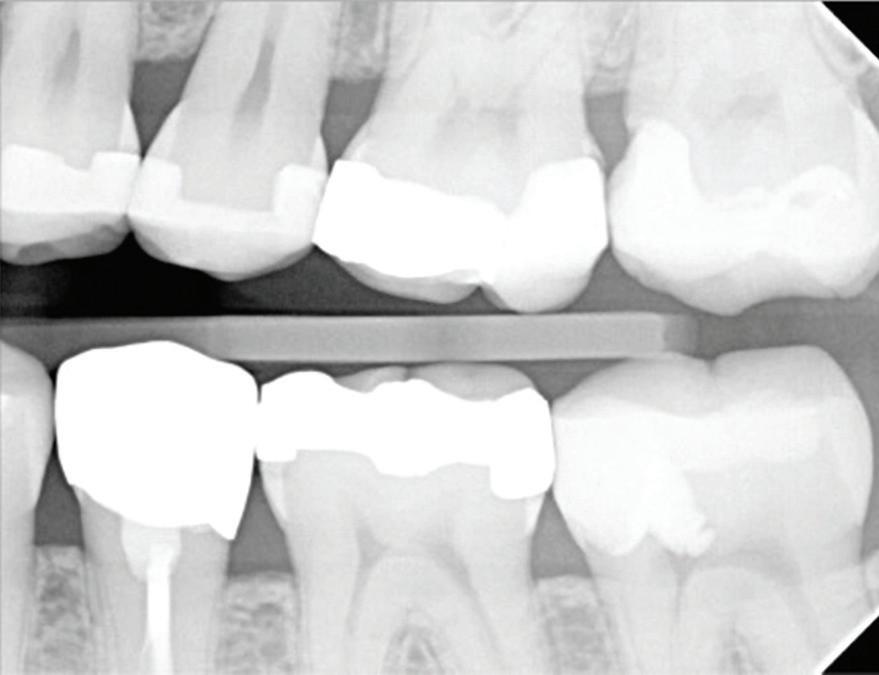

These CAIPP lesions are best identified and monitored with high-resolution CBCT scans (Fig 5). However, even advanced CBCT systems, with voxel sizes as small as 0.075 mm, are not capable of reliably detecting cracks, which are typically much narrower.45 Therefore, the presence of a CAIPP defect, combined with careful clinical diagnostics and evaluation, remains the most reliable indirect indicator of a crack with radicular extension.

The presumed clinical significance of a lingering CAIPP defect is that the persistent biofilm in the crack can lead to further periodontal breakdown and symptoms. However, the changes in these areas were monitored over the course of

previous studies, and these bony lesions did not progress over time and remained asymptomatic.4,26 Together, these studies demonstrated that the persistent bony defect adjacent to the cracks may remain stable and asymptomatic over time, making saving teeth with this technique a realistic option for patients.

Fig 5. CBCT images of a crack-associated isolated periodontal pocketing defect associated with a distal crack in the mandibular right first molar. A. Sagittal view showing angular crestal bone loss (arrow) along a distal radicular crack at the cervical margin. B. CBCT 3-dimensional rendering showing the defect (arrow) at the distal root. C. Axial view showing the defect (arrow) at the distal root.